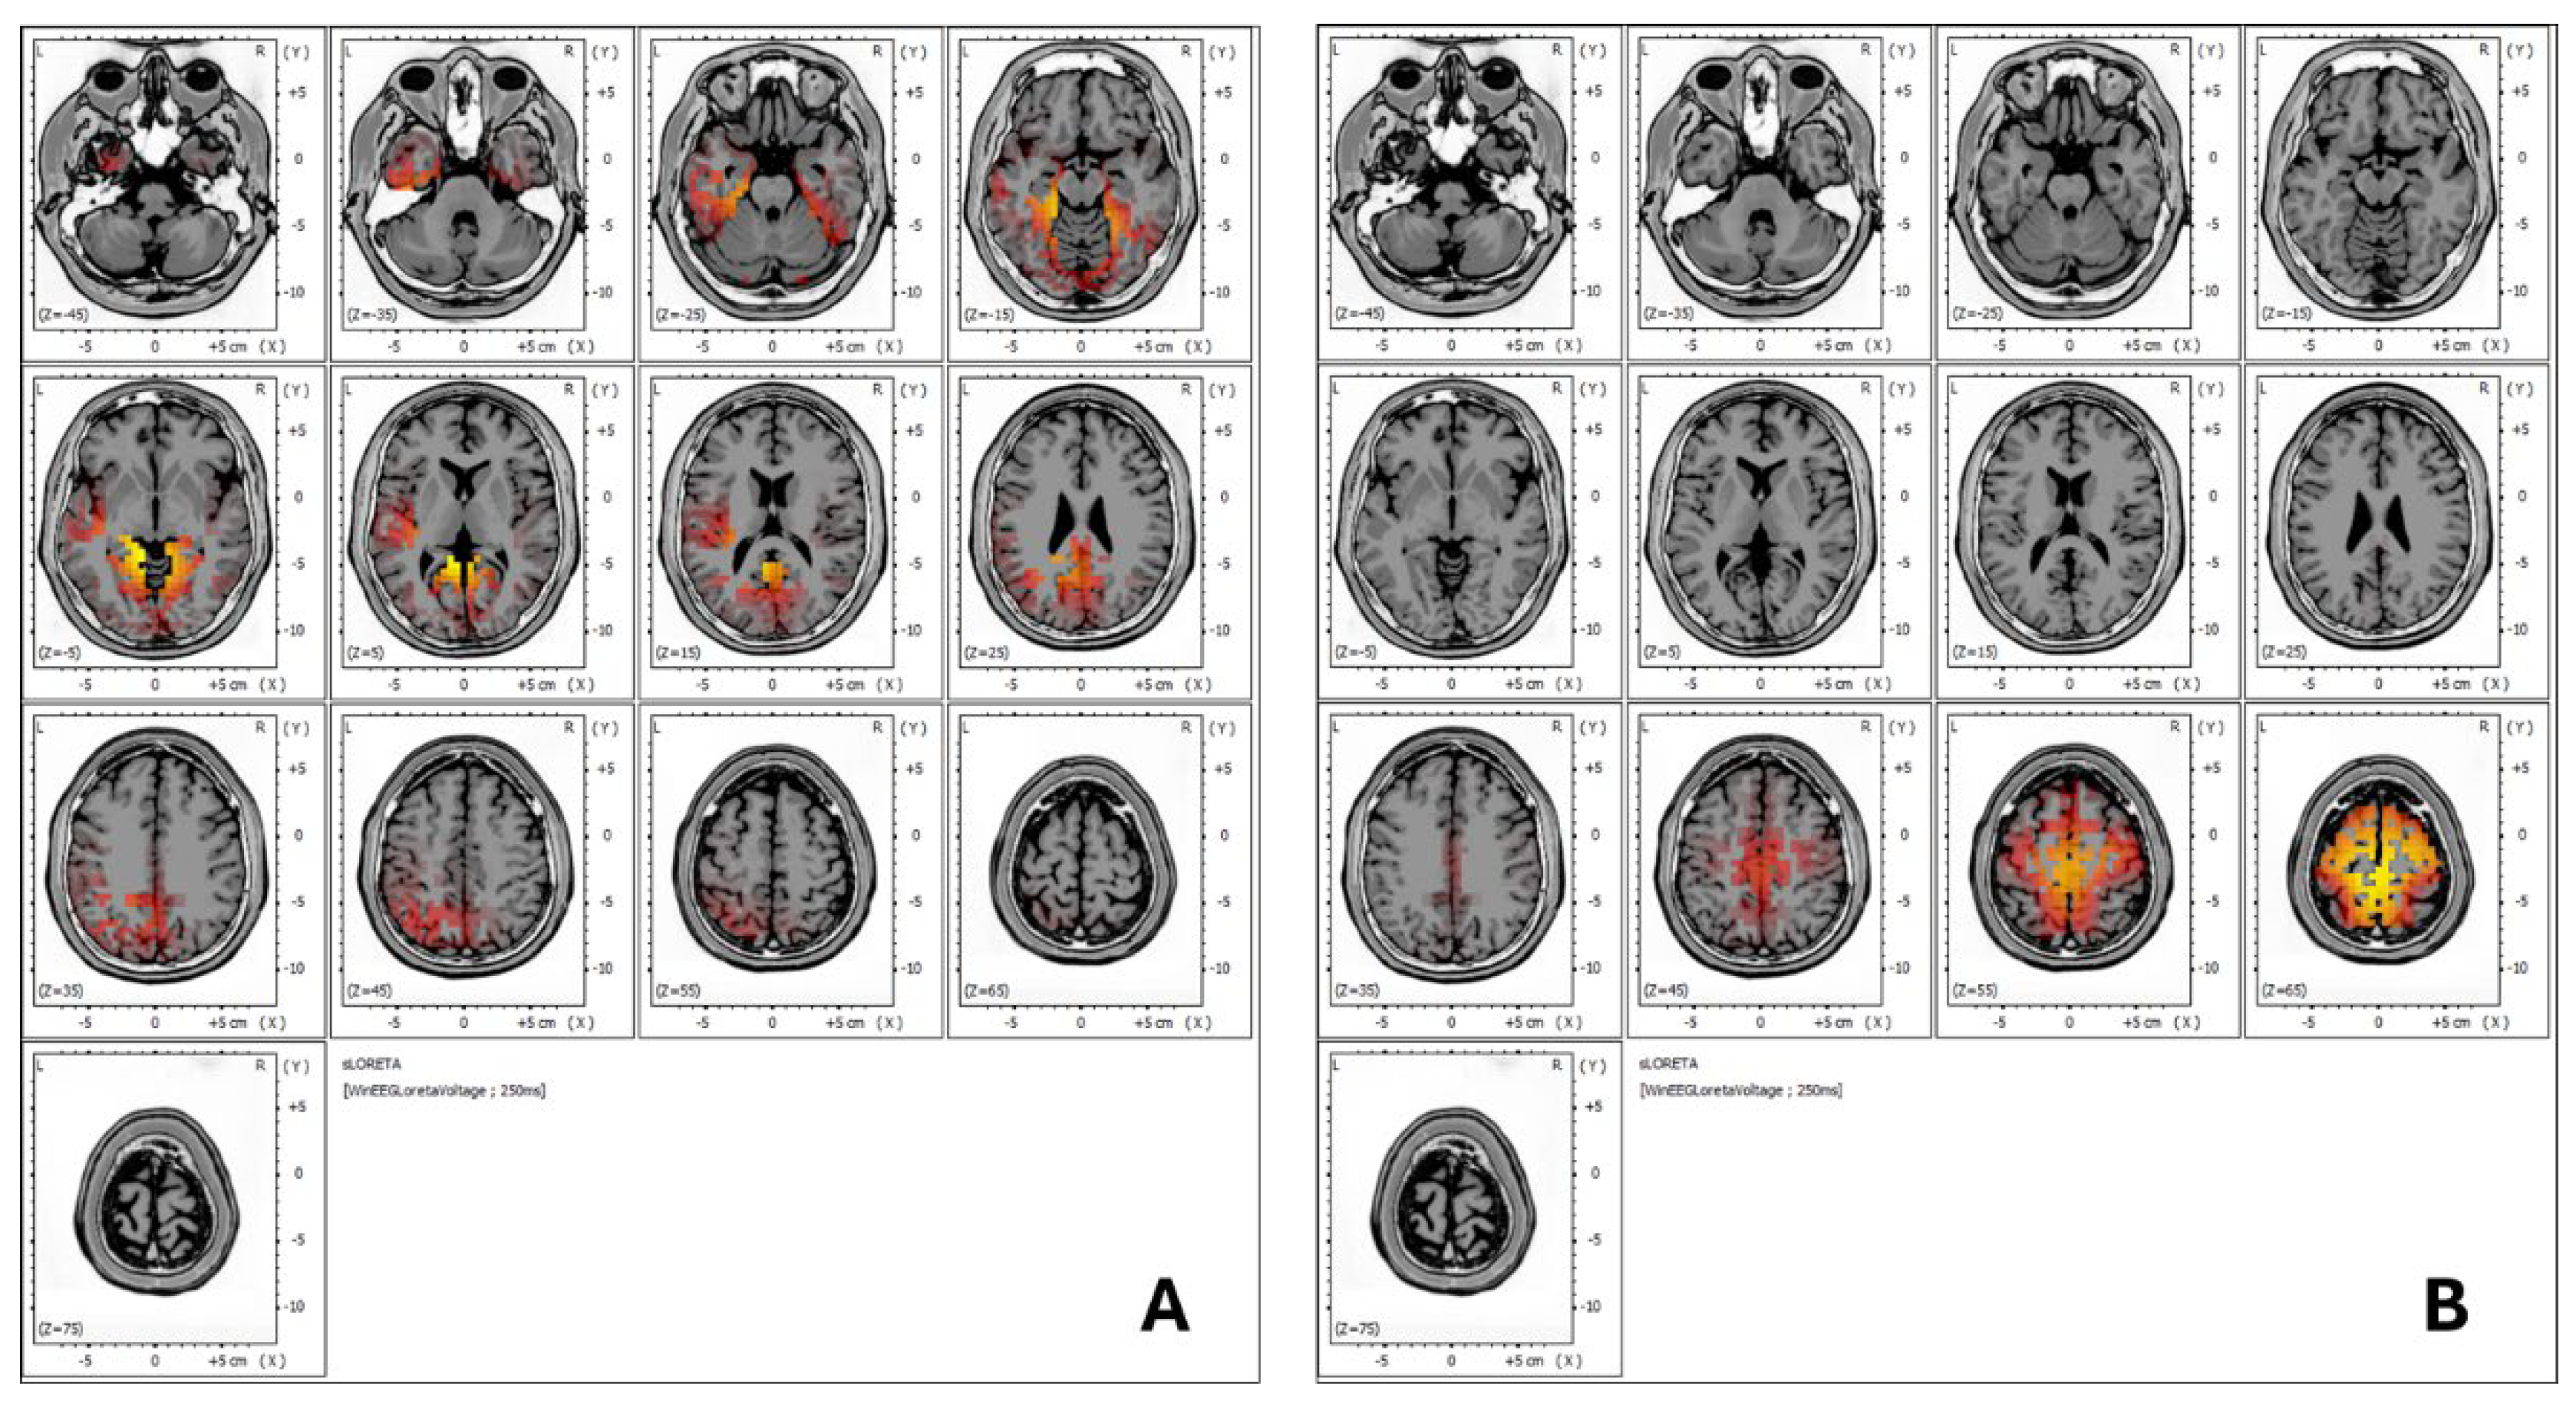

3.1.4. sLORETA Analysis

sLORETA (standardized Low-Resolution Brain Electromagnetic Tomography) analysis is a neuroimaging technique used to estimate the three-dimensional distribution of brain wave activity within different regions of the brain [14]. By providing a spatial representation of electrical activity, sLORETA allows researchers and clinicians to identify specific brain areas involved in various cognitive, sensory, and emotional processes. This technique offers valuable insights into how different brain regions are activated under certain conditions or in response to treatment.

In Figure 4, the sLORETA analysis demonstrates notable changes in brainwave activity before and after treatment. Figure 4A shows that, prior to treatment, the patient exhibited brainwave activity across a range of frequencies, from slower waves (delta and theta) to faster frequencies, including an alpha rhythm at 12.45 Hz. These were localized in Brodmann areas 30, 19, 29, 27, and 18, which are linked to functions such as emotional regulation, receptive language, auditory processing, semantic analysis, visual information processing, and sentence formation.

After the treatment, as shown in Figure 4B, there was a more extensive distribution of frequencies across the prefrontal cortex, motor regions, and both the anterior and posterior cingulate gyrus. Notably, the slow delta and theta rhythms previously present in the temporal areas (Brodmann areas 21 and 42) were no longer observed. Clinically, this change correlated with improved tolerance to wet noises, which allowed the patient to integrate more comfortably into public environments, such as restaurants, indicating enhanced auditory processing and emotional regulation.

Figure 4. LORETA analysis. Figure 4A: The patient exhibited brainwave activity across a spectrum of frequencies, ranging from slower waves (delta and theta) to faster frequencies, including an alpha rhythm at 12.45 Hz. These were observed in Brodmann areas 30, 19, 29, 27, and 18. These regions are mainly associated with functions such as emotional regulation, memory encoding (verbal semantic, face, image, auditory), working memory, facial emotional perception, emotional experience and regulation, and visual information processing. Figure 4B: Following treatment, a more widespread frequency distribution was noted in the motor and somatosensory cortex areas, with improvement in working memory processing, visuospatial attention, and motor execution.